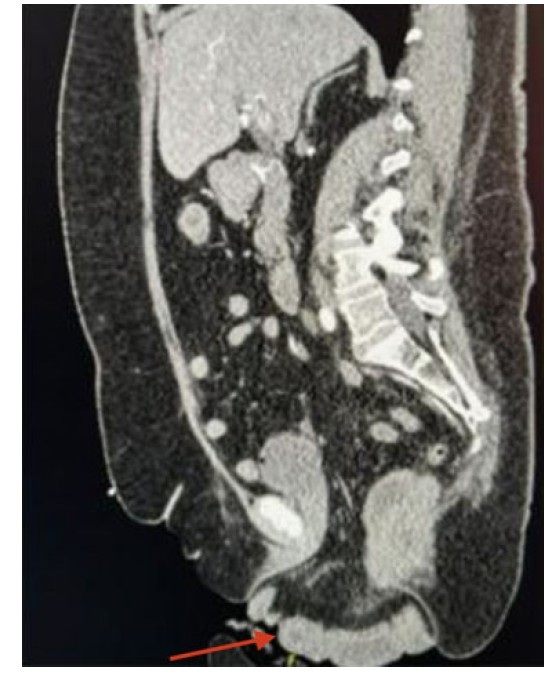

On examination, the patient appeared uncomfortable. The eviscerated bowel appeared strangulated/ischemic (Figure 1). The patient remained hemodynamically stable. Computed tomography (CT) showed evidence of pelvic floor prolapse with peritoneal fat and nondilated loops of small bowel and rectosigmoid colon extending through the vagina (Figure 2).

Figure 2: CT pelvis with IV contrast showing evidence of pelvic floor prolapse with peritoneal fat and nondilated loops of small bowel and rectosigmoid colon extending towards the vaginal canal (red arrow).